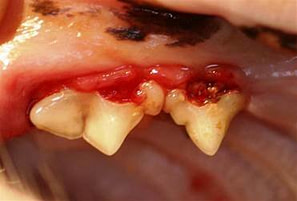

FORL’s are lesions on the teeth themselves, and range from barely penetrating the enamel at the neck of a tooth right above the gum line, to full-blown loss of the entire crown with gum tissues growing over the remaining root tip. The molars and premolars are most commonly affected, but these lesions can appear on any tooth and on any surface of a tooth.

The teeth become functionally destroyed as sections of tooth are re-absorbed leaving areas of exposed tooth tissue below the enamel and weakened roots. These lesions were originally called feline “neck lesions” or cat “cavities” because the tooth damage is typically observed in the “neck” region of the tooth where the tooth meets the gum line.

Neck lesions can appear as areas of reddened tissue at the tooth-gum interface almost as if the gum (gingival) tissue is growing into the tooth or is covering over the base of the tooth. In some cases, there appears to be a “hole” or ‘concavity’ in the tooth (see above picture)

Once the outer layer of enamel is gone, the teeth may become quite painful to the touch. The actual ring-like lesions can be seen, if you can examine the cat’s mouth. Teeth may break off at the damaged sites, and cats sometimes show “jaw chattering” if the area is touched, due to pain. Many cats will not eat well because of the discomfort.